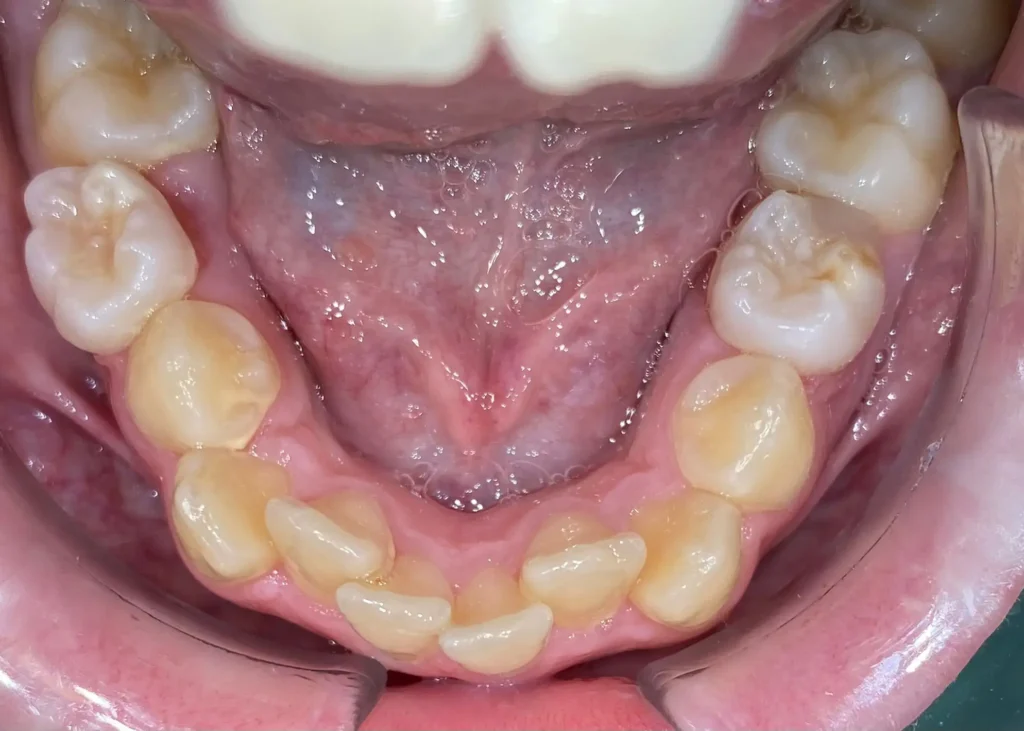

Casos clínicos de ortodoncia en CDPA